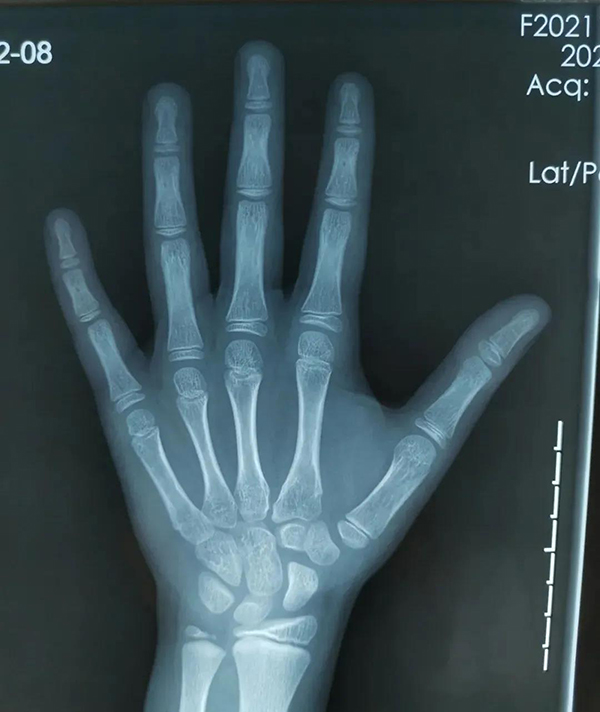

評估骨齡最常見的方法是拍攝左手(包含全掌和腕部)X 光正位片。具有操作簡便、檢查時(shí)間短、檢查費(fèi)用低的特點(diǎn),故目前仍以 X 線平片作為骨齡評估的主要手段。臨床上評估骨齡以左手及腕關(guān)節(jié)作為最常見的評測部位,通過觀察相應(yīng)的腕部骨化中心、左手掌指骨骨化中心的個(gè)數(shù)、形態(tài)來評估骨齡。因此,獲得用于骨齡評估的左手及腕關(guān)節(jié)的圖像是骨齡評估的第一步。骨齡圖像的關(guān)鍵骨化中心包括遠(yuǎn)端橈骨、遠(yuǎn)端尺骨、腕骨。

徐州市婦幼保健院為準(zhǔn)確測算骨齡,由放射科專業(yè)人員攝片獲取標(biāo)準(zhǔn)X線片圖像,通過準(zhǔn)確定位,清晰拍攝,保證手腕骨的影像質(zhì)量。另外,醫(yī)院還引進(jìn)了先進(jìn)的骨齡影像智能檢測系統(tǒng),該系統(tǒng)依據(jù)臨床常用指標(biāo)(包括兒童身高體重,父母身高等參數(shù)),可自動(dòng)生成詳細(xì)完善的診斷報(bào)告,包含骨齡評價(jià)、身高評價(jià)、發(fā)育評價(jià)、身高預(yù)測等指標(biāo)。隨后,結(jié)合專業(yè)骨齡讀片醫(yī)生人工讀片,既能夠保證結(jié)果的精準(zhǔn)度,同時(shí)也能夠提高讀片的效率。